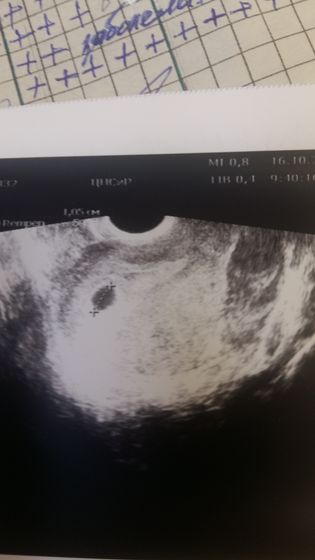

Итак сходила я сегодня на УЗИ. Наконец то увидели ПЯ )) Сказали ставить утрожестан 200 для подстраховки и прийти через 2 недели посмотреть сердцебиение))